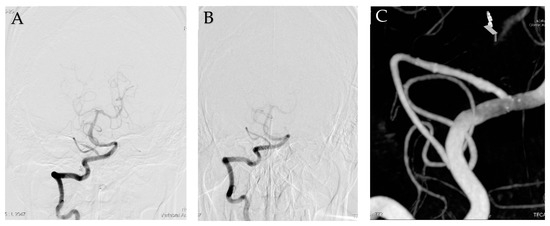

2. Case Report